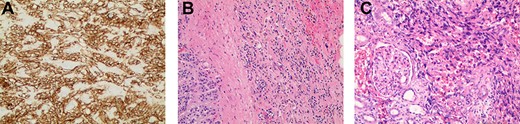

(A) Immunostaining for CD31 (100×) strongly marked lesional cells, supporting the diagnosis of AS and excluding sarcomatoid RCC; (B) routine H&E-stained section (100×) demonstrating an infiltrative pattern sarcomatoid tumor with variable cellularity and characteristic slit-like spaces, including red blood cells, characteristic of AS; benign adrenal tissue is visible on the left; (C) routine H&E-stained section (100×x) demonstrating angiosarcomatoid pattern with benign glomeruli.

The resected tissue was stained with routine hematoxylin–eosin (H&E) and was immunostained with CD31 (Fig. 2a–c). Histological examination of the resected left kidney and adrenal gland revealed high-grade, multifocal AS with sarcomatoid and rhabdoid features and extensive tumor necrosis. The margins of the ureter, renal vasculature and soft tissue were negative for malignancy. The sarcoma involved the tissue surrounding the adrenal gland but abutted the adrenal capsule. The tumor was staged as Stage IV, Grade 3 and T3N1M0. Examination of the resected periaortic lymph node revealed AS with involvement of one lymph node and adjacent perinodal soft tissue.